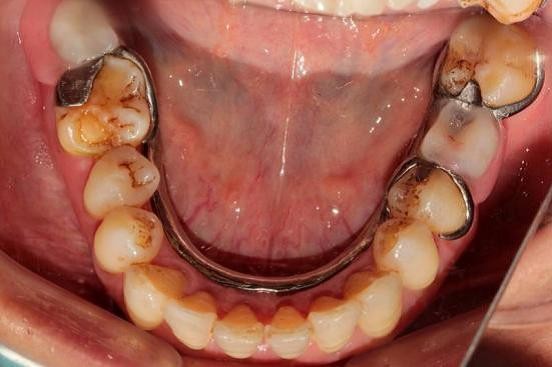

3、龋病

口内存在自然牙的街坊进行活动假牙装装配,需要磨除一定的健康邻牙组织做支撑,从而导致当细菌、牙垢的堆积发酵,产生的酸性物质,更易腐蚀被磨除一定牙体组织的牙齿,从而导致牙齿出现龋坏。